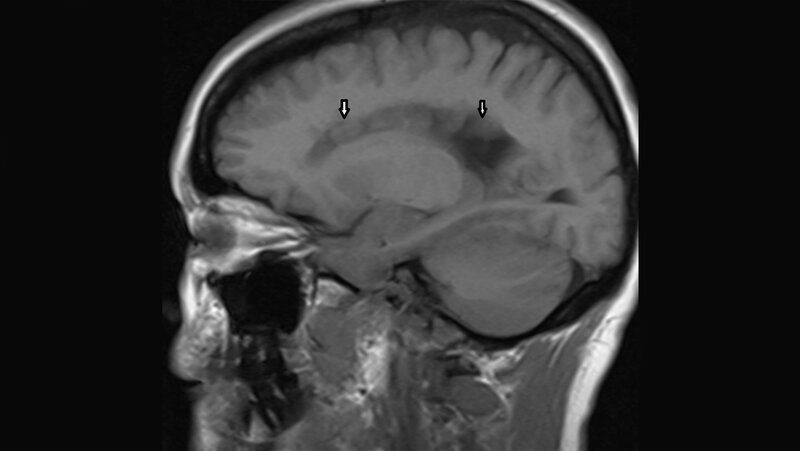

Anomalien und Normvarianten – Zerebrale Malformation 1.7: Heterotopie

Die Heterotopie ist die am häufigsten vorkommende Anomalie der kortikalen Entwicklung. Die Migrationsstörungen führen klinisch oft zu epileptischen Anfällen, die psychomotorische Entwicklung der subependymalen Heterotopie ist normal. Es werden 3 unterschiedliche Formen unterschieden.

Heterotopia is the most frequently occuring anomaly affecting cortical development. Neuronal migration disorders often clinically characterized by epileptic seizures as well as normal psychomotor development in many cases of subependymal type. There are three different types.